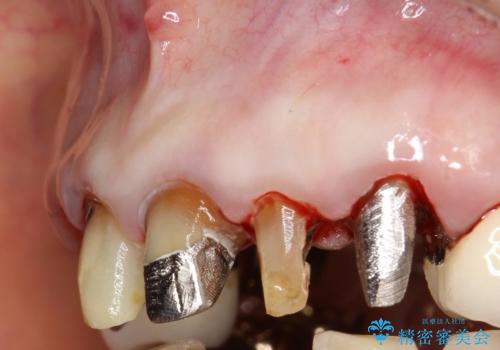

前歯の低クオリティな治療の実態 妥協無い治療で根本からやり治す

・虫歯がとりきれていない

・接触部分がガタガタで適合の悪い金属

・全く無菌の努力がされていない根管治療

など、いい加減な治療は「治療」ではなく、むしろ医原性に歯の寿命を短くします。